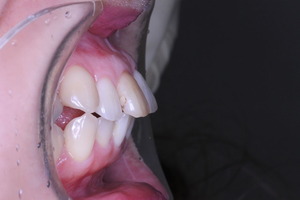

患者さんの主訴は口元をひっこめたいでした。

そうなると抜歯しての歯列矯正治療は必須です。また、口元の改善を考えると、前歯よりの歯を抜歯したほうが治療的には容易です。

しかしながら、いつ治療したか記憶にない銀歯があります。神経もとってしまってますし、中がどのような状態になっているか把握できません。治療中に歯がとれてしまい、結果的に抜歯となってしまう可能性もございます。

それでは治療経過です

少し経過が進みました

治療開始から3年経過した現在の状況です